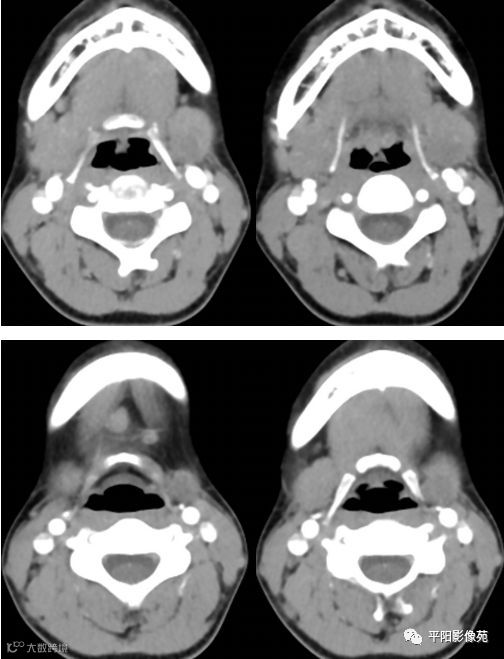

影像表现:

CT:左侧颌下腺增大,其内后下方可见类圆形等密度影,增强扫描轻度强化,动脉期CT值约50Hu,静脉期CT值约61Hu,边界欠清,大小约1.6cmX1.3cm。增强扫描右侧颌下腺形态完整,密度均匀,边缘光滑,周围脂肪间隙清晰,颈I区可见明显肿大淋巴结,较大者约1.0cmX0.8cm。